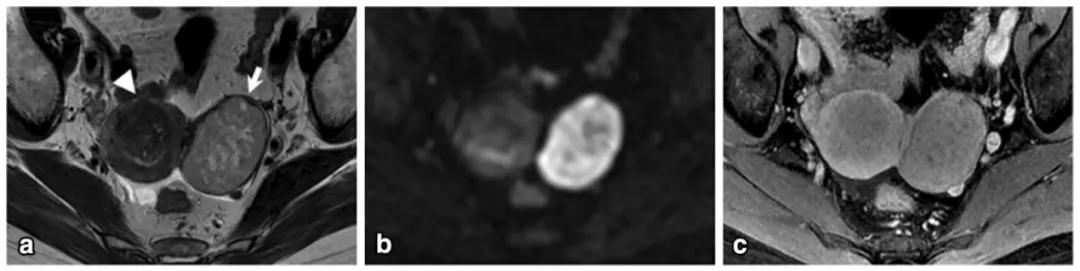

女,22 岁,无性细胞瘤。乳酸脱氢酶及碱性磷酸酶升高。T2WI 示右侧卵巢分叶状肿物(图 a),DWI 呈高信号(图 b),增强扫描明显强化(图 c)。箭头显示肿物内可见纤维血管分隔。